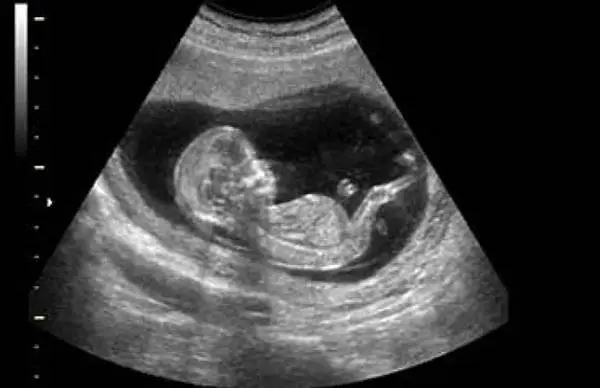

مدیر گروه ایمنی‌شناسی تولید مثل پژوهشگاه ابن‌سینا گفت: حدود سه میلیون زوج نابارور در کشور وجود دارد و سالانه ۵ درصد به این آمار افزوده می‌شود و متاسفانه این موضوع به تهدیدی برای امنیت جمعیتی ایران تبدیل شده است.

امیرحسن زرنانی، مدیر گروه ایمنی شناسی تولید مثل پژوهشگاه ابن‌سینا جهاددانشگاهی در دومین روز از نمایشگاه دستاوردهای جهاد دانشگاهی در نشست فرآورده‌های نوین درمانی در بیماری‌های صعب العلاج و ناباروری گفت: در طول ۵۰۰ میلیون سال تکامل، هیچ ویژگی‌ای به اندازه تولیدمثل با سازگاری موجودات زنده پیوند نخورده است. در واقع هر گونه‌ای که نتواند تولیدمثل کند، محکوم به نابودی است و از همین‌رو، تولیدمثل اساس تکامل تمام گونه‌های زنده را تشکیل می‌دهد.

زرنانی با بیان اینکه گونه‌هایی که در فرایند تولیدمثل موفق‌تر هستند، شانس بقا و تکامل بیشتری دارند، اظهار کرد: بدن انسان تنها در یک شرایط خاص یعنی در رحم مادر توانایی پذیرش بافتی نیمی از آن که متعلق به فرد دیگری است را دارد و این پدیده، یکی از عجایب زیست‌شناسی است که پایه‌ مطالعات ایمنی‌شناسی تولید مثل را شکل داده است.

او در تشریح اهمیت این حوزه توضیح داد: ایمنی‌شناسی تولید مثل به این پرسش پاسخ می‌دهد که چرا بدن مادر، جنینی را که نیمی از مواد ژنتیکی‌اش متعلق به پدر است، طرد نمی‌کند. هرگونه اختلال در این سازگاری طبیعی می‌تواند منجر به سقط جنین یا ناباروری شود.

مدیر گروه ایمنی‌شناسی تولید مثل پژوهشگاه ابن‌سینا تأکید کرد: ناباروری تنها یک مسئله پزشکی نیست، بلکه چالشی اجتماعی است. مطالعه‌ای که حدود ۱۲ تا ۱۳ سال پیش در پژوهشگاه ابن‌سینا روی ۱۹ هزار زوج از سراسر کشور انجام شد نشان داد که حدود ۱۹.۷ درصد زوج‌های ایرانی نابارور هستند؛ به عبارتی از هر ۶ زوج، یک زوج با مشکل ناباروری مواجه‌اند.

مدیر گروه ایمنی‌شناسی تولیدمثل پژوهشگاه ابن‌سینا با استناد به داده‌های ملی اظهار کرد: در حال حاضر حدود سه میلیون زوج نابارور در ایران وجود دارد. طبق مطالعات، از هر شش زوج ایرانی، یک زوج با ناباروری مواجه است و سالانه حدود پنج درصد به این آمار افزوده می‌شود.

او افزود: افزایش سن ازدواج و تأخیر در فرزندآوری از عوامل اصلی این روند است. اکنون میانگین سن ازدواج از ۱۸ تا ۲۲ سال در دهه‌های گذشته به بالای ۲۸ سال رسیده است. همزمان، نرخ رشد جمعیت کشور به ۱.۶ رسیده که کمتر از نرخ جایگزینی است و این زنگ خطر جدی برای آینده جمعیتی ایران محسوب می‌شود.